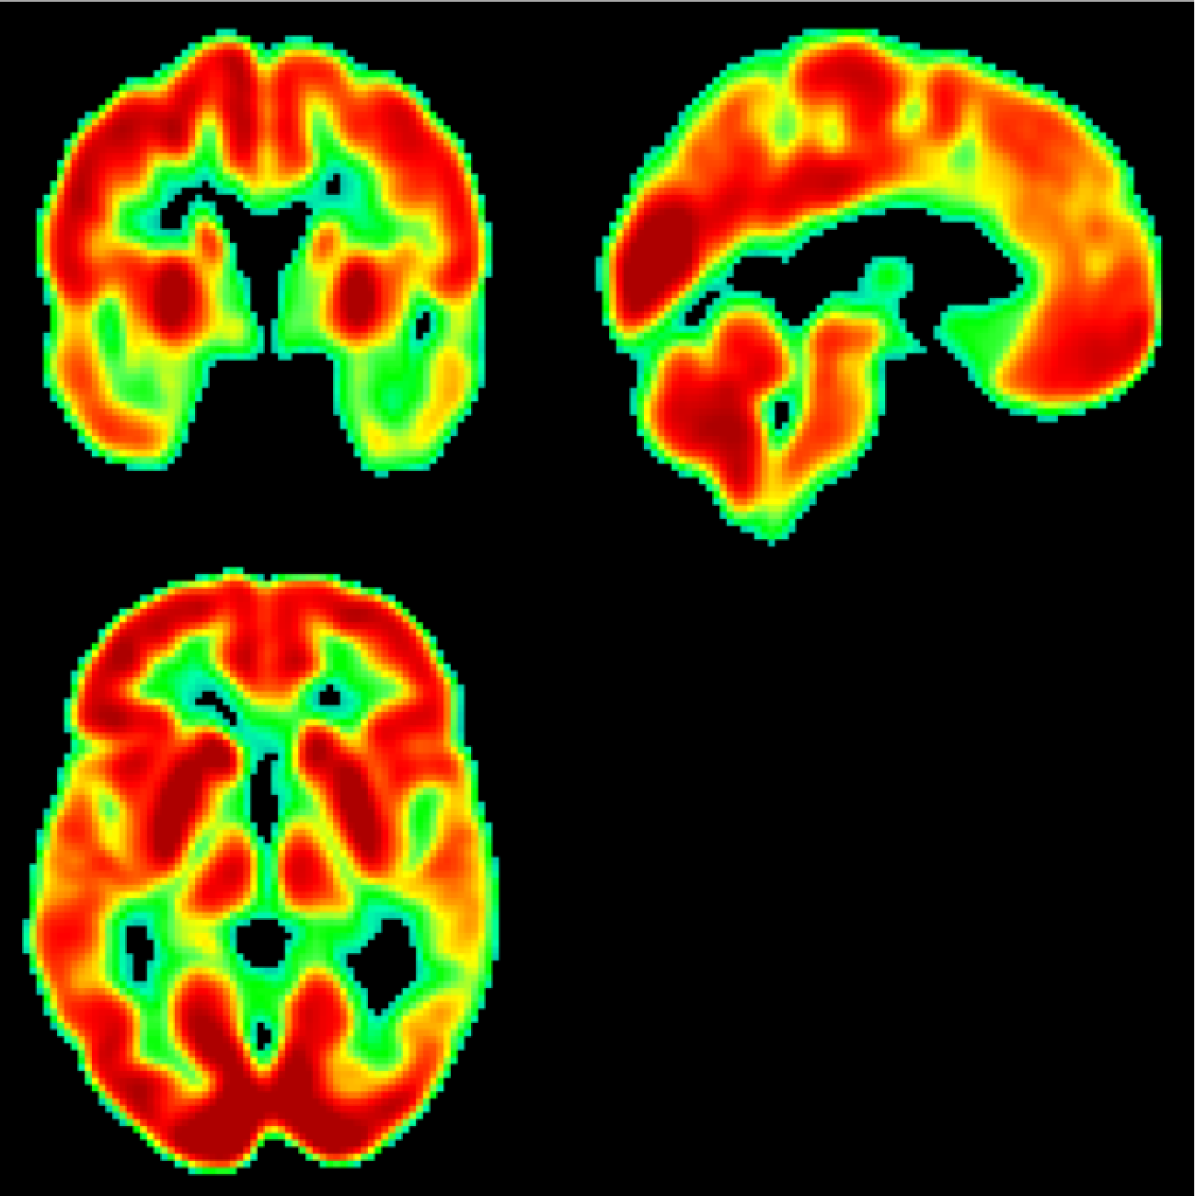

AD main effect is progressive neurological damage resulting from neuronal loss which occurs first in the hippocampus, temporal cortices, and parietal cortices [18, 19] (see Figure 1). As the disease evolves, neural damage progresses and affects the parahippocampal gyrus and amygdala [20]. In advanced stages, AD affects brain regions involved in primary bodily functions, complicating vital movements and becoming fatal to the patient [2]. Caused by the presence of neuritic plaques [21] and neurofibrillary tangles [22] in the affected neurons, this progressive neurological damage translates into neuropsychological and behavioural manifestations including worsened capacity to recall information, problems with planning and decision-making, generalized confusion, delusions, hallucinations, repetition of conversations, anxiety, among others [23, 2]. In addition, AD is typically accompanied by comorbidities such as major depressive disorders [24] which complicate the already poor situation of the patient, aggravating perceived health in a self-sustained downward spiral as proposed by recent life-course models [25] and contributing to severe reductions in life expectancy and other diffuse effects on health and well-being [26].

Figure 1: Regions of interest for research on early AD diagnosis in the human brain: hippocampus (red), temporal cortices (blue), and parietal cortices (green).